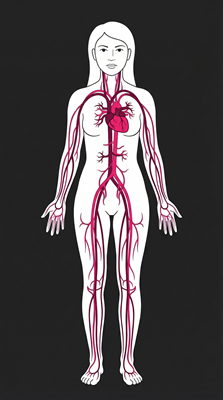

Cardiovascular Support

Unsaturated fatty acids (especially linoleic acid) may help lower cholesterol levels and reduce risk of heart disease.